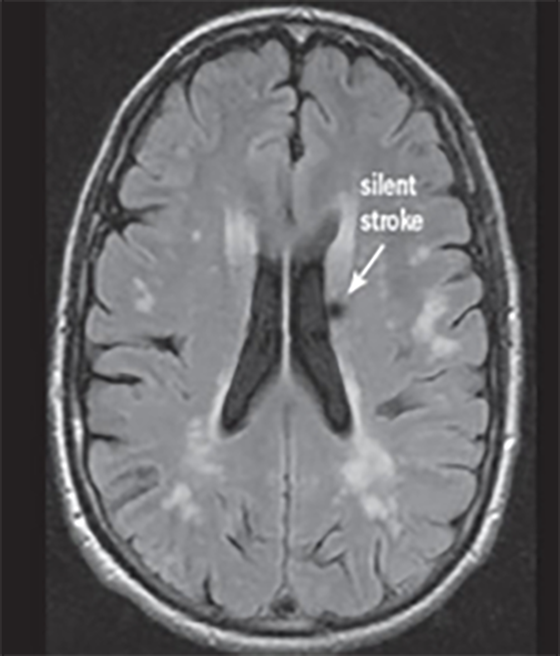

Deși unele tipuri de infarct sunt aparente pentru ochiul liber neprofesionist (Fig.2), altele sunt mai subtile și mult mai reduse în intensitatea aparentă și dimensiune (Fig.3 & Fig.4).

În imaginile din figurile 2-4 se pot vedea cu ochiul liber abnormalitățile la nivelul creierului din imaginile RMN. Astfel de cazuri reprezintă o parte importantă din setul de date, iar restul imaginilor e compus din cazuri mult mai greu de identificat sau clasificat chiar și pentru radiologii cu experiență. Pentru moment suntem departe de a concura cu precizia și acuratețea radiologilor, dar soluțiile de detecție automată de astfel de leziuni vor să vină în ajutorul medicilor. Un medic radiolog interpreta în jur de 679 imagini de tip RMN per zi în anul 2010 [9]. De atunci cantitatea de imagini produse de aparatura medicală e în continuă creștere iar presiunea asupra radiologilor crește și ea, iar cu aceasta cresc și șansele de eroare sau de ratare a unor leziuni importante. O soluție automată vine ca un adjuvant pentru radiolog asigurându-se că acestuia nu îi scapă niciun caz clar de leziune, iar radiologul se poate axa pe cazurile cu adevărat dificile și importante. Și în plus, un algoritm nu suferă de oboseală și nici nu necesită repaus.

Fig. 3 Simulare detecție de infarct cerebral lacunar acut din RMN-DWI. Ref: [7]